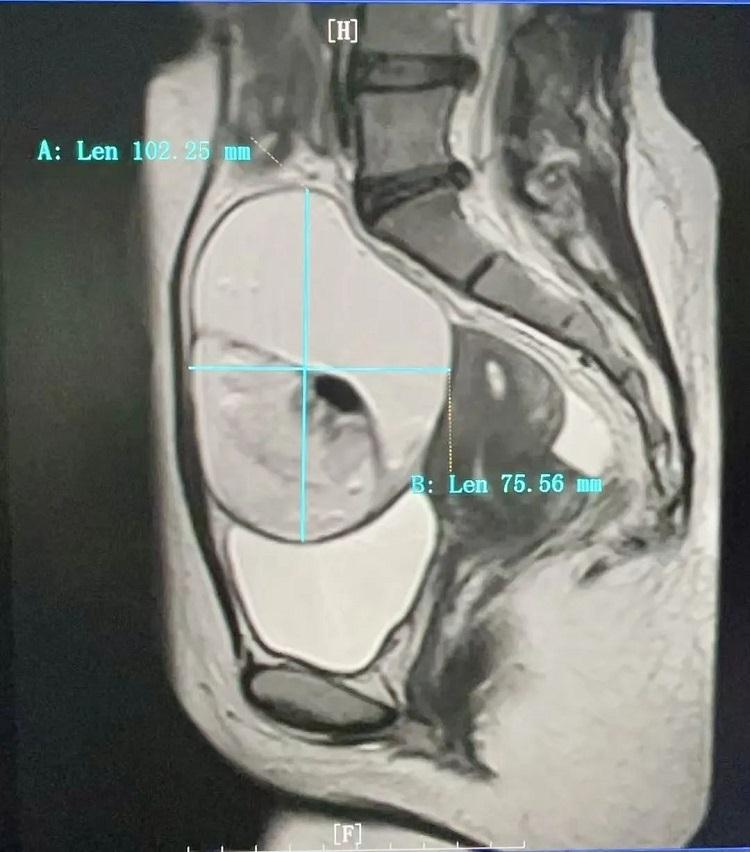

在山東濟(jì)南工作的小熙因持續(xù)下腹部不適,在山東當(dāng)?shù)蒯t(yī)院初診考慮婦科疾患,多方打聽到新近調(diào)任我院的副院長劉達(dá)賓主任醫(yī)師、副教授擅長婦科疾病診治,慕名從山東奔赴三千里前來我院求診。劉達(dá)賓主任醫(yī)師接診后迅速對(duì)小熙進(jìn)行了專業(yè)詳細(xì)的問診、體檢及相關(guān)影像學(xué)檢查。一查婦科彩超及盆腔MRI,結(jié)果讓小熙及親人均大吃一驚,姑娘瘦弱的身體里居然藏著一個(gè)直徑約11cm左右的巨大腫物,子宮后方的巨大囊實(shí)性腫物幾乎占據(jù)了整個(gè)盆腔,手術(shù)難度極大!

盆腔核磁檢查影像考慮到小熙的年齡和生育意愿,還有小熙對(duì)手術(shù)后留疤以及對(duì)生育功能潛在影響的擔(dān)憂,劉達(dá)賓主任醫(yī)師組織團(tuán)隊(duì)開展術(shù)前討論,決定采用更為先進(jìn)、微創(chuàng)的手術(shù)方式進(jìn)行治療。在劉達(dá)賓主任醫(yī)師的帶領(lǐng)下,手術(shù)團(tuán)隊(duì)?wèi){借精湛的技術(shù)和默契的配合,成功實(shí)施單孔腹腔鏡卵巢腫瘤剝除手術(shù)。該術(shù)式不僅最大限度保護(hù)了患者的生育功能,同時(shí)也兼顧美觀,達(dá)到雙贏效果。“